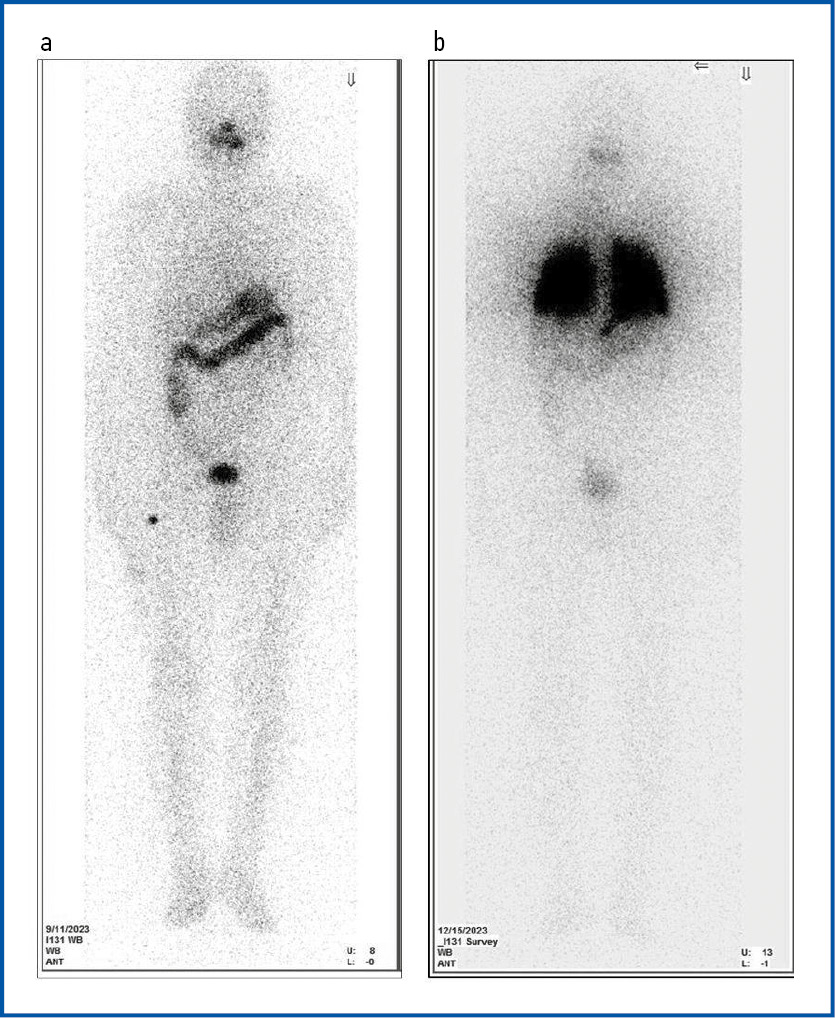

В сентябре 2023 г. проведен 2-й курс РЙТ в ФГБУ «НМИЦ эндокринологии» активностью 131I 5,35 ГБк. На момент терапии уровень ТГ составил 315 нг/мл, на фоне ТТГ – 92 мМЕ/л. На птСВТ, несмотря на высокодозную терапию 131I, накопление радиофармацевтического препарата (РФП) отсутствовало (рис. 2, a). С целью поисков дополнительных возможностей ТТ выполнено молекулярно-генетическое исследование блоков с первичной опухолью: выявлена мутация V600E в гене BRAF, PD-L1 позитивный статус; патогенных транслокаций ALK, NTRK не выявлено.

С 26 октября по 10 декабря 2023 г. пациенту проводили терапию дабрафенибом (BRAF-ингибитор) в дозе 150 мг 2 раза в сутки и траметинибом (MEK-ингибитор) в дозе 2 мг/сут. Через 6 нед приема ТТ выполнена дСВТ с 70 МБк 131I: в области грудной клетки отмечалось симметричное высокоинтенсивное накопление РФП, включение в легкие составляло 55% от счета над всем телом.

Предположена редифференцировка опухоли на фоне терапии, принято решение о выполнении повторного курса высокодозной РЙТ. В декабре 2023 г. проведена РЙТ активностью 131I 7,21 ГБк на фоне 4-недельной отмены левотироксина натрия. На момент терапии показатель ТТГ составил 44 мМЕ/л, ТГ – 214 нг/мл, антител к ТГ – 17,27 МЕ/мл (<115).

По данным птСВТ: в проекции ложа ЩЖ очаги гиперфиксации РФП не определяются. В проекции грудной клетки определяется интенсивное симметричное накопление 131I. Включение в легкие составляет 38,7% от счета над всем телом (см. рис. 2, b).

Рис. 2. Посттерапевтическая сцинтиграфия всего тела: а – после 2-го курса РЙТ (до редифференцировки, сентябрь 2023 г.); b – после 3-го курса РЙТ (после редифференцировки, декабрь 2023 г.).

Fig. 2. Post-treatment whole-body scintigraphy: a – after the 2nd course of radioactive iodine therapy (before redifferentiation, September 2023); b – after the 3rd course of radioactive iodine therapy (after redifferentiation, December 2023).